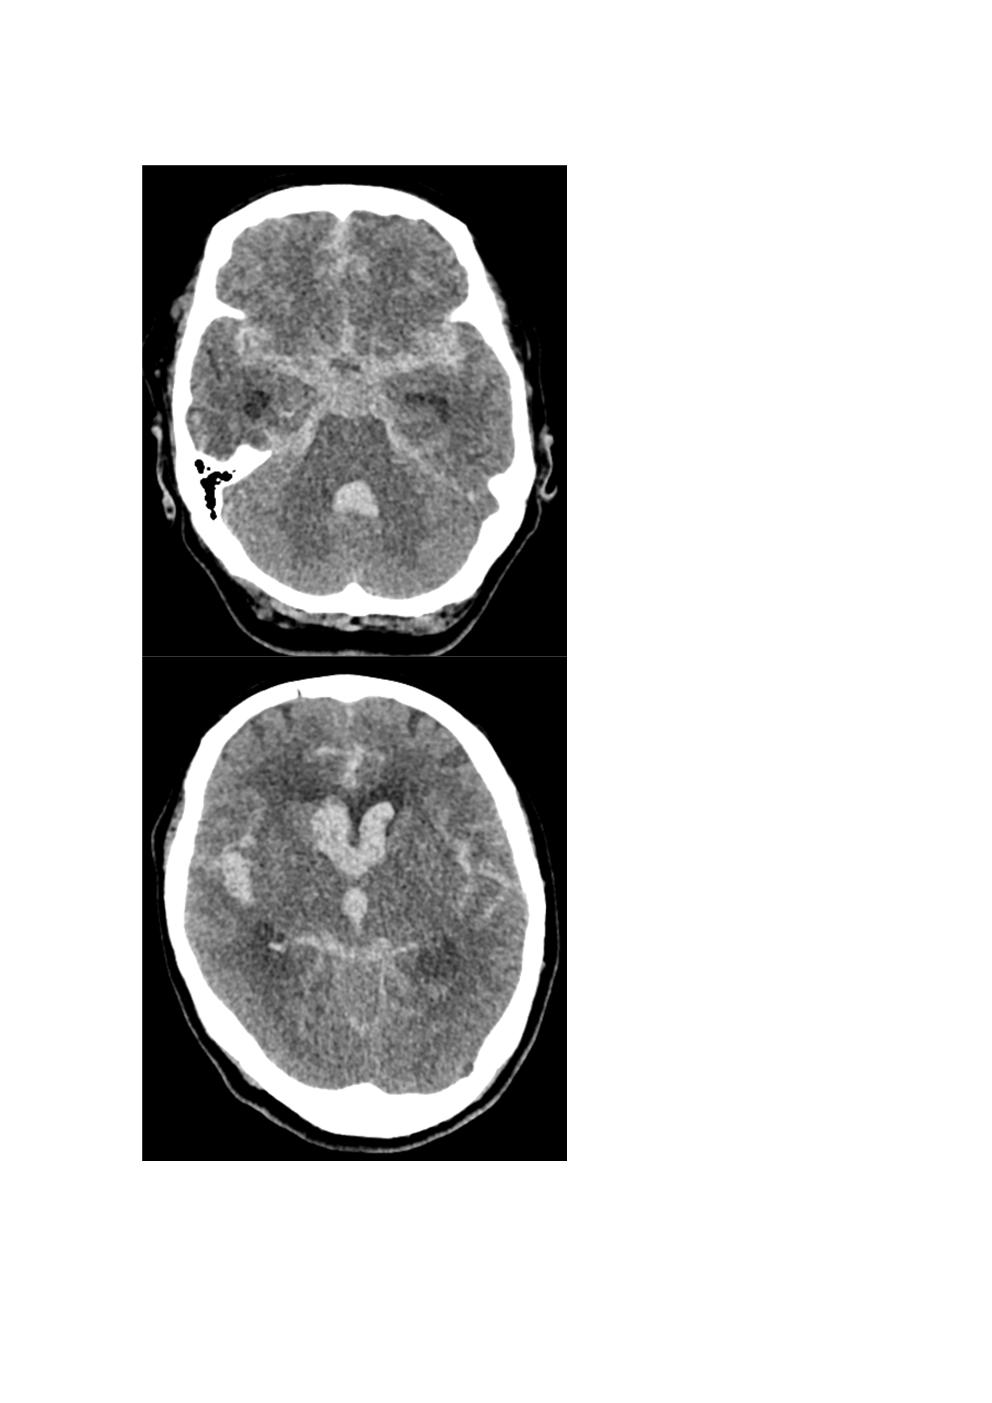

- 뇌 CT(Computed Tomography) 영상에서 출혈의 양과 분포를 기준으로 SAH의 중증도를 평가하는 척도입니다.

- Fisher 등급이 높을수록 뇌혈관연축(Cerebral Vasospasm)의 위험이 증가합니다.

| Grade 3 | 1mm 이상의 두꺼운 지주막하 출혈 | 높음 |

| Grade 4 | 뇌실 내 출혈(IVH) 동반 또는 심한 SAH | 매우 높음 |

- 의의: Fisher Grade는 뇌혈관연축(Vasospasm) 발생과의 연관성을 평가하는 데 유용하며, 치료 계획을 세우는 데 도움을 줍니다.